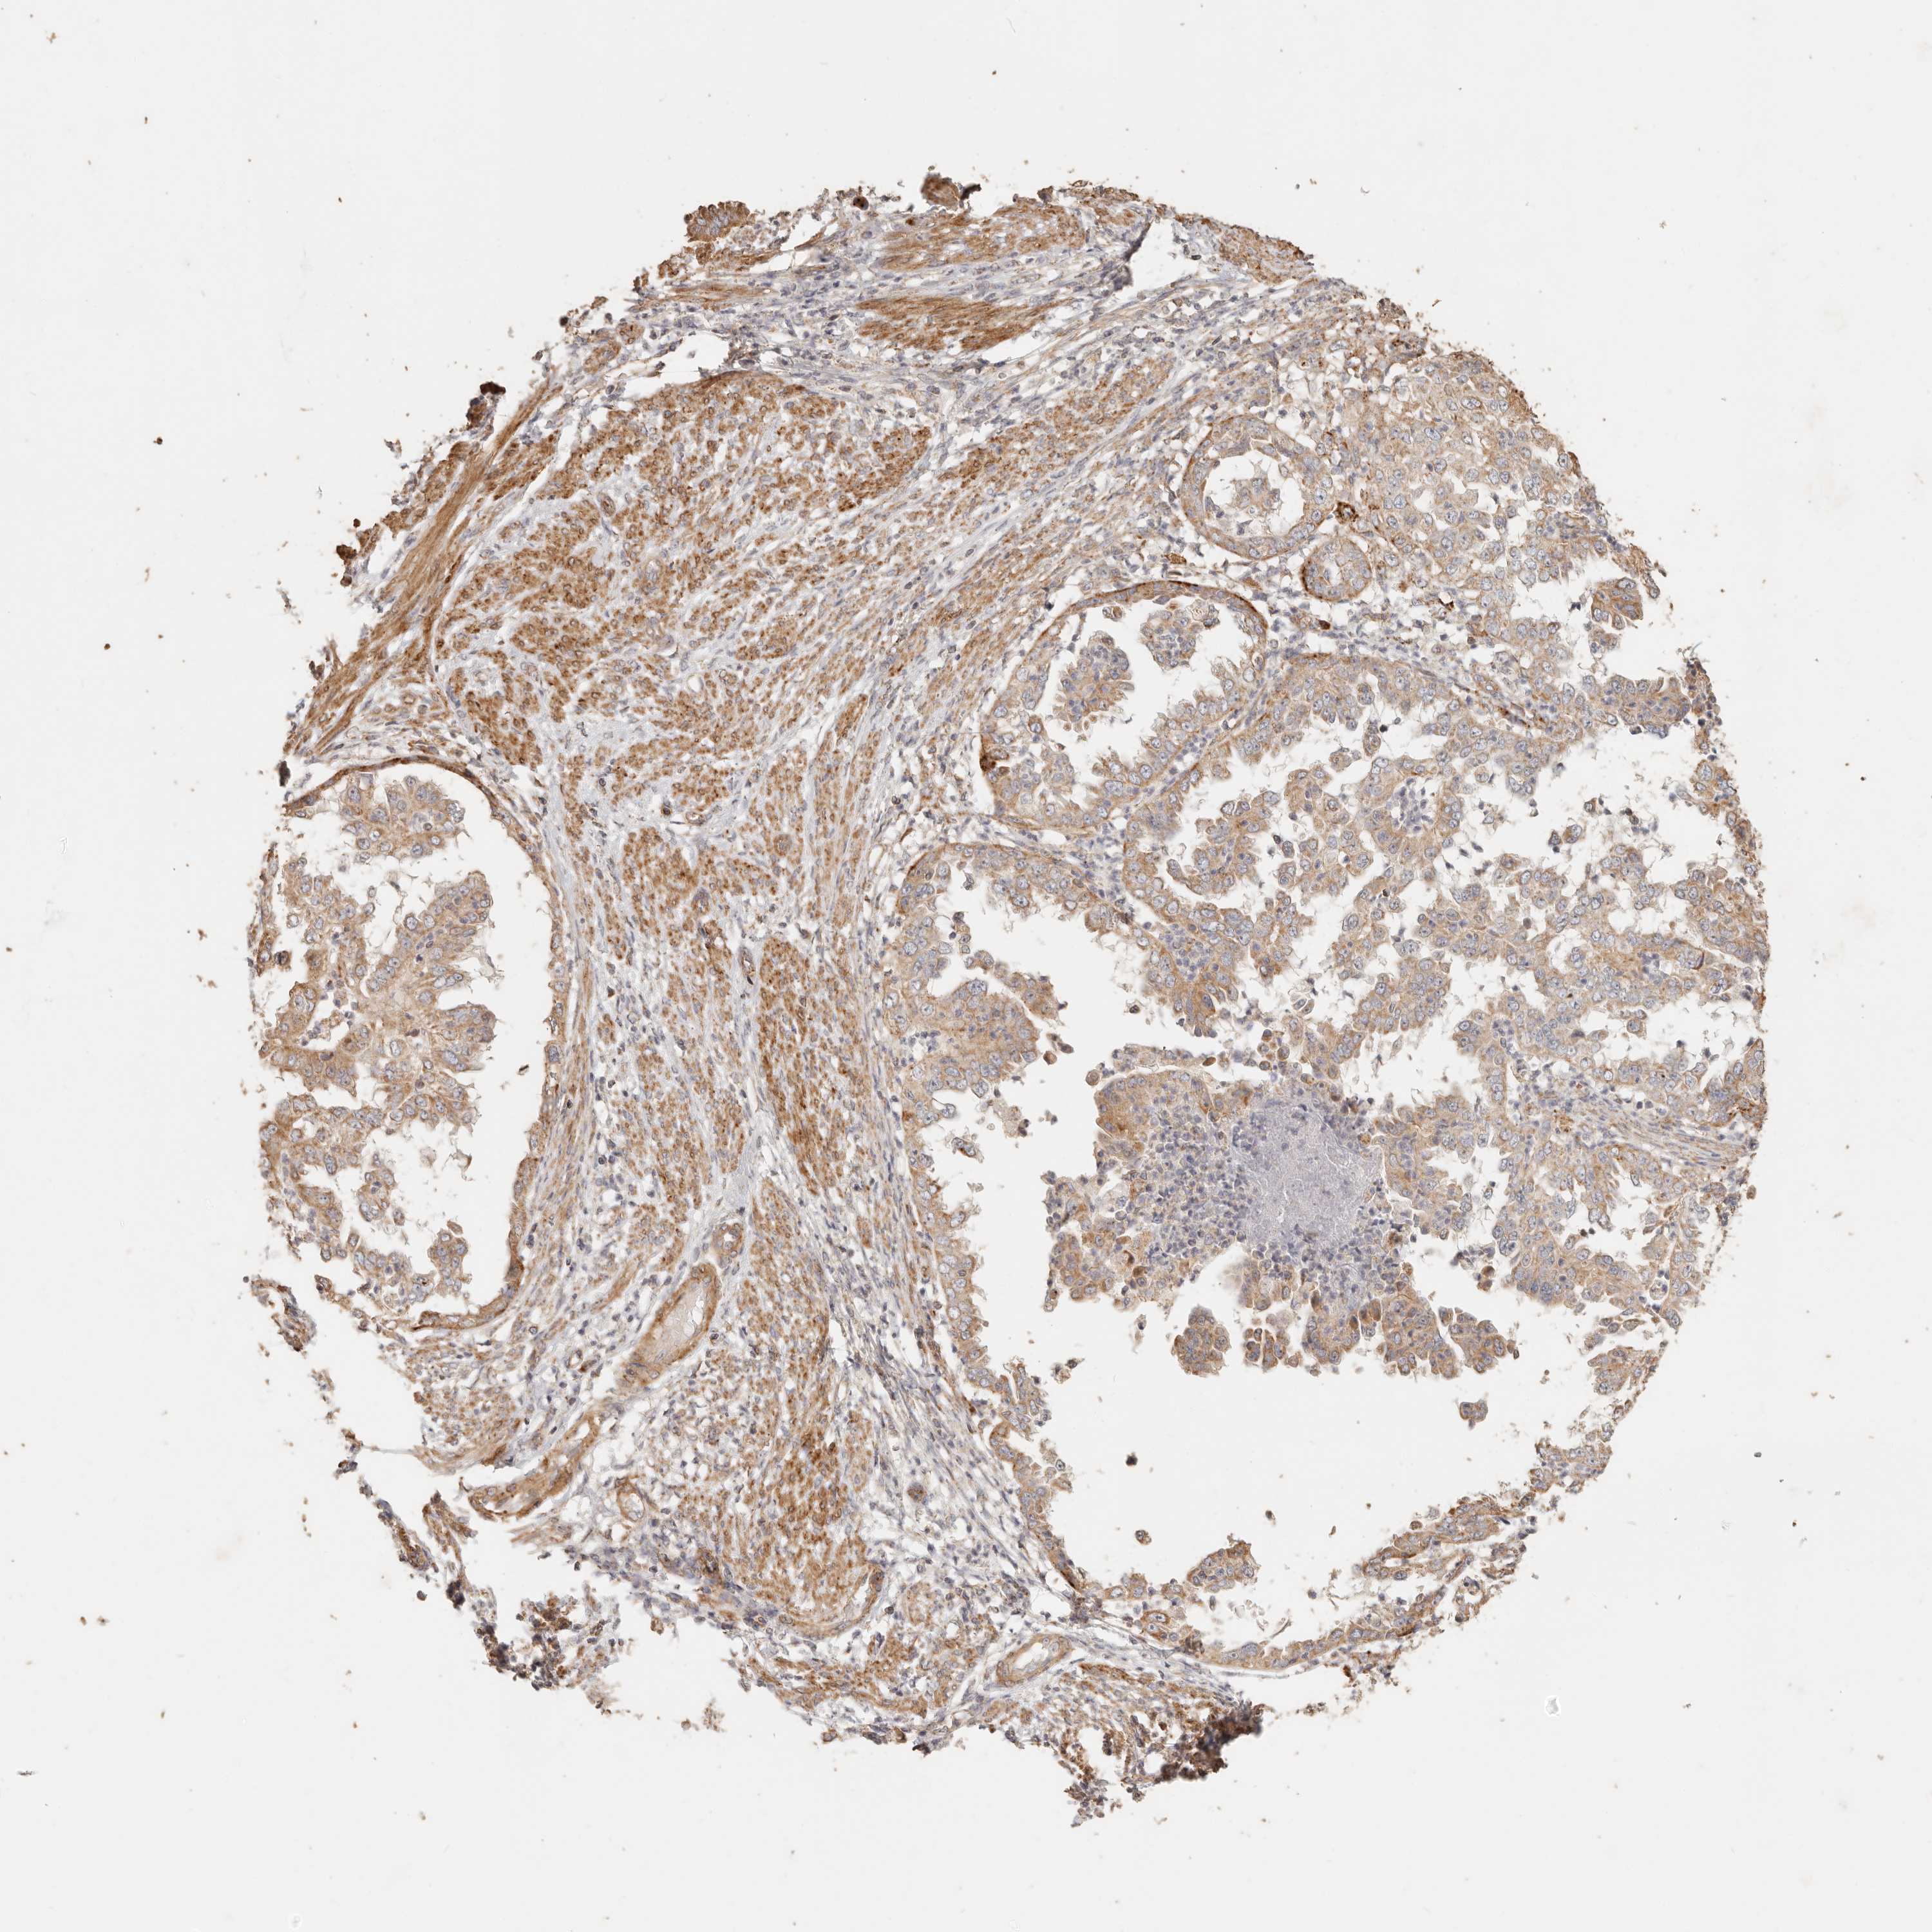

ENDOMETRIAL CANCER - Protein expressioni

A mouse-over function shows sample information and annotation data. Click on an image to view it in a full screen mode. Samples can be filtered based on level of antibody staining by selecting one or several of the following categories: high, medium, low and not detected. The assay and annotation is described here.

Note that samples used for immunohistochemistry by the Human Protein Atlas do not correspond to samples in the TCGA dataset.

Antibody stainingi

Antibody staining in the annotated cell types in the current human tissue is reported as not detected, low, medium, or high, based on conventional immunohistochemistry profiling in selected tissues. This score is based on the combination of the staining intensity and fraction of stained cells.

Each image is clickable and will lead to virtual microscopy that enables deeper exploration of all samples and also displays staining intensity scores, fraction scores and subcellular localization as well as patient and tissue information for each sample.

Antibody HPA004912

Antibody HPA013350

Antibody CAB012209

Staining

High

Medium

Low

Not detected

Intensity

Strong

Moderate

Weak

Negative

Quantity

>75%

75%-25%

<25%

None

Location

Nuclear

Cytoplasmic/membranous

Cytoplasmic/membranous,nuclear

Adenocarcinoma, NOS

Adenocarcinoma, metastatic, NOS